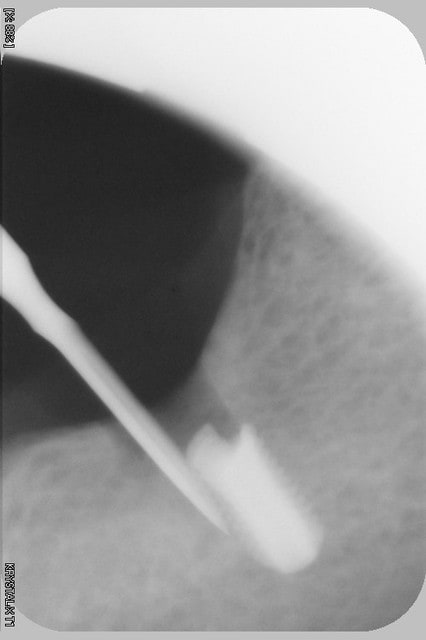

Bonjour alice, tu n'y es pour rien dans ce qui t'es arrivé. Voilà le même cas que le tien avec une importante lésion apicale sur une couronne datant de plus de 20 ans. Curetage minutieux et implantation plusieurs mois après. La suite est identique à la tienne. Sur le même patient mais sur la 36, la même lésion, même implantation et exactement la même suite. Pensant comme toi à une erreur de protocole et de toutes les salades dont on t'abreuve sur eugénol, sur la 46, j'ai remis un implant 4 mois après et même suite, j'ai compris et j'ai arrêté. C'est uniquement lié à l'infiltration de ton os par cette très vieille lésion et dont on a beaucoup parlé lors de mes formations en implanto.

Céramik, l'extraction ainsi que le curetage ont été faits un an avant l'implantation. C'était mon premier cas avec une lésion ancienne. Aujourd'hui j'ai compris et si cela m'arrive j'en parlerais des risques avec le patient.

Le but de mon post c'est d'éviter l'autoflagellation à certains de mes confrères en montrant que dans un site "douteux" comme tu dis et très ancien, on a beau prendre toutes les précautions ce n'est pas un gage de réussite et que le risque de péri implantite existe toujours malgré un bon curetage.

L'extraction a été faite en Février 2010 et la pose en Mai 2011. Quant à la crête j'avais 10mm de large et aucune table lésée. Un cas idéal.